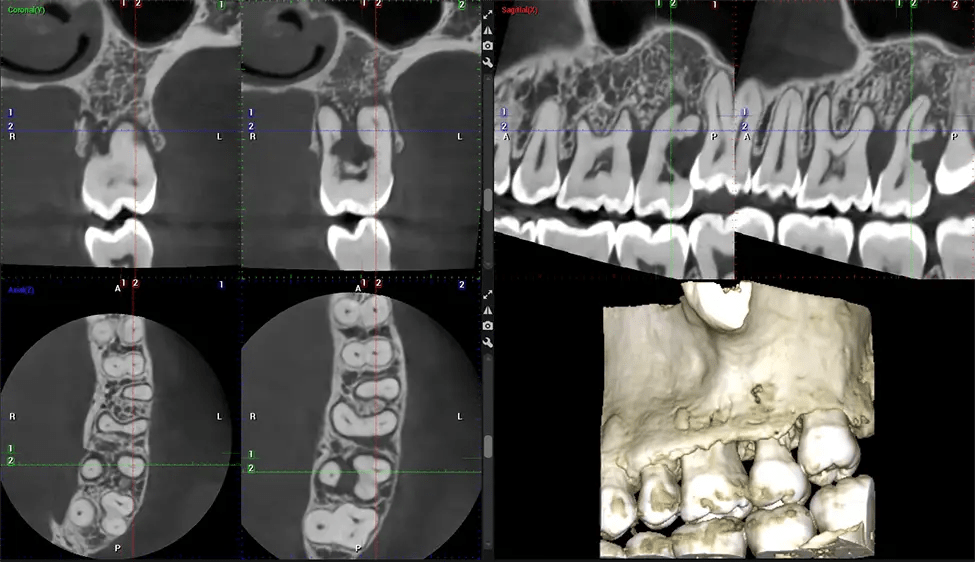

Esta exploración 3D, llamada tomografía computarizada de haz cónico, le brinda a su dentista una imagen más completa de su anatomía bucal y sus procesos patológicos que una radiografía tradicional. A diferencia de las radiografías convencionales, que capturan una imagen 2D de la boca desde varios ángulos, una exploración 3D toma varias radiografías digitales para una imagen. Proporciona una vista completa de la mandíbula, los dientes, los nervios y los tejidos blandos. Esta vista mejorada permite a los dentistas detectar problemas menores que no son visibles en las exploraciones 2D tradicionales, como muelas del juicio impactadas o fracturas óseas en la cavidad sinusal.

Otro beneficio importante es que las imágenes 3D proporcionan imágenes más precisas de la estructura ósea. Estas imágenes son más detalladas y le brindan un diagnóstico más preciso. Un diagnóstico preciso significa un mejor tratamiento para usted.

Después del proceso de escaneo, las imágenes de rayos X capturadas son procesadas por el software CBCT, que aplica algoritmos para reconstruir una imagen 3D detallada del área escaneada. El software recopila estas imágenes de rayos X individuales y crea una representación digital en 3D de la anatomía del paciente. El dentista o el radiólogo pueden ver y analizar la imagen CBCT 3D reconstruida. Esta imagen se puede manipular, rotar y acercar o alejar para examinar estructuras específicas y evaluar la condición del paciente.